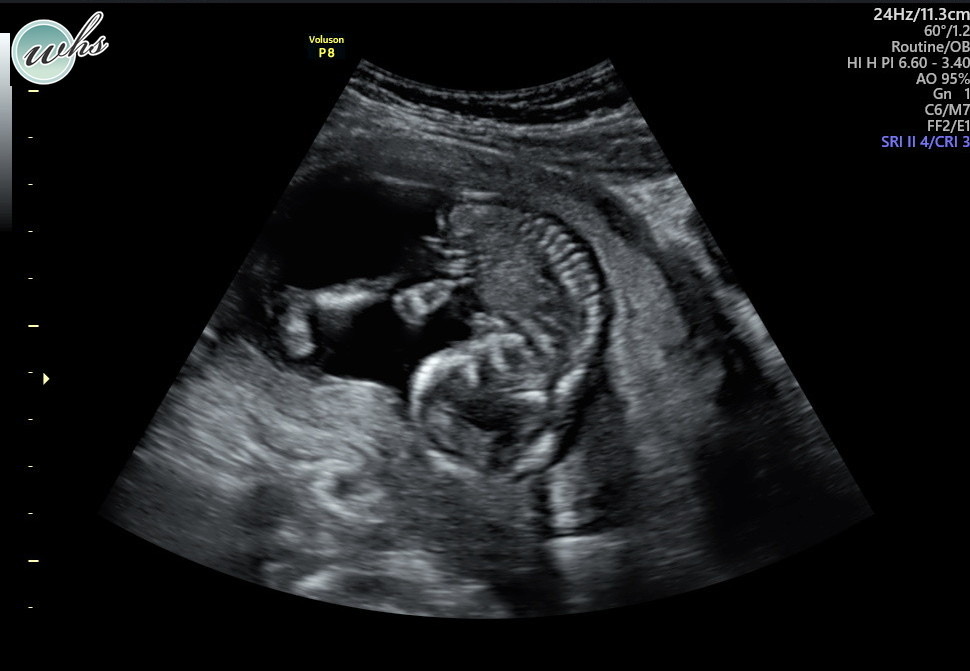

I will never forget how difficult it was to see our girl on the screen, all squished in there without the fluid needed around her to keep her safe and healthy.

My husband was with me through FaceTime, but he was at home about 20 minutes away. He rushed to me as quickly as he could, and I swear to you time stopped. Time stopped for us while it continued for everyone else in the world around us. Our baby was alive, her heart was beating, she was measuring at 20 weeks… but she had very little fluid around her. Time stopped and tears fell when our OBGYN told us how serious this was and while we waited to see a specialist.

Over the course of the next week and a half we would learn so much. Visits with specialists would initially offer hope… she was perfectly developed and had a small amount of amniotic fluid, but likely not enough. They called it Oligohydramnios. And over time our hope would become less and less… without fluid our daughter would never develop her lungs properly and it was only a matter of time until an infection called Chorioamnionitis could kill both our baby and myself. I was urged to take my temperature several times a day and watch myself closely for signs of infection. For a week and a half I spent most of my time in bed, desperately searching for success stories and any indication that things could still turn out ok. I’d visit Labor and Delivery frequently to check for leaking amniotic fluid, and somehow it was never detected. The only explanation we ever received was that the amniotic sac must’ve been compromised when I had the Subchorionic Hematoma and I had a slow leak over a long period of time. I tried IV fluids, supplements, and drank so much water in effort to help increase the amniotic fluid around her. But every ultrasound became more and more bleak. The fluid was decreasing and she was unable to move. I could feel her hiccup, but she could not move. It’s truly gut wrenching to see your baby this way.

We traveled from Dallas to Houston to seek another opinion and search for any innovative, experimental means to offer some help. There was nothing we could do. Humans can land rovers on Mars but cannot patch up an amniotic sac.